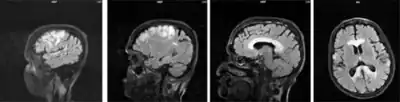

| This condition affects the corpus callosum | |

Marchiafava–Bignami disease is routinely diagnosed with the use of an MRI because the majority of clinical symptoms are non-specific. Before the use of such imaging equipment, it was unable to be diagnosed until autopsy. The patient usually has a history of alcohol use disorder or malnutrition and neurological symptoms are sometimes present and can help lead to a diagnosis. MBD can be told apart from other neural diseases due to the symmetry of the lesions in the corpus callosum as well as the fact that these lesions don't affect the upper and lower edges.[4]